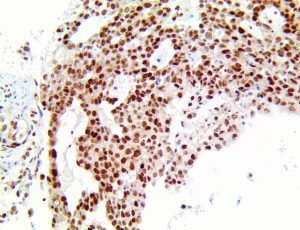

It is the ICU physician who is most likely to witness one of the deadliest manifestations of the abnormal immunological response, the cytokine storm syndrome (CSS). This response is also referred to by some as the cytokine release syndrome (CRS). CSS is characterized by continuous activation and expansion of macrophage and lymphocyte populations, which secrete large amounts of cytokines, causing the cytokine storm. This massive cytokine release is akin to hemophagocytic lymphohistiocytosis (HLH) disease, a syndrome characterized by initial unchecked and persistent activation of cytotoxic T lymphocytes and NK cells.

Clinical and laboratory manifestations of HLH include fever, enlarged liver and/or spleen, neurologic dysfunction, coagulopathy, liver dysfunction, cytopenias (i.e., low levels of erythrocytes, leukocytes, and/or platelets), hypertriglyceridemia, hyperferritinemia, hemophagocytosis, and eventually diminished NK cell activity as the immune system becomes progressively paralyzed. HLH can be familial (primary HLH) or secondary to another disease process (sHLH), such as rheumatic disease, in which it is referred to as macrophage activation syndrome (MAS, characterized by elevated ferritin).